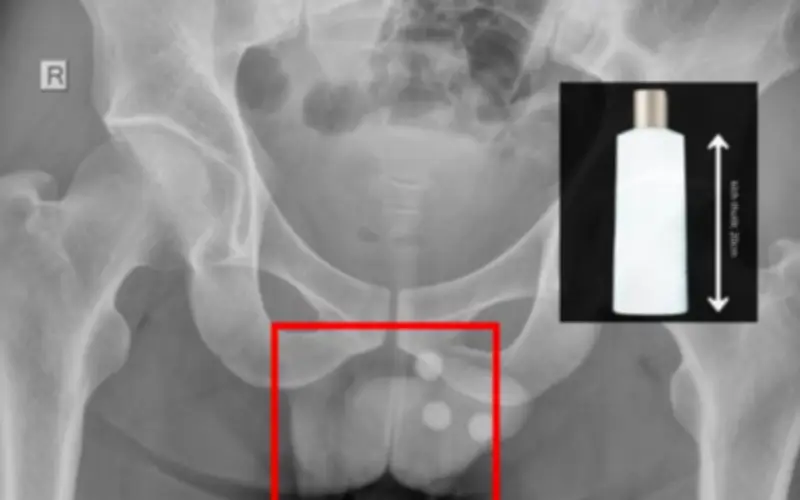

Chai nhựa dài 20cm mắc kẹt trong trực tràng, bác sĩ cảnh báo biến chứng nguy hiểm

Một trường hợp y tế hy hữu vừa được ghi nhận khi một người đàn ông phải nhập viện trong tình trạng đau bụng dữ dội và khó chịu ở vùng hậu môn. Sau khi tiến hành kiểm tra và chụp chiếu, các bác sĩ đã phát hiện một vật thể lạ có kích thước lớn mắc kẹt trong trực tràng của bệnh nhân.

Vật thể được xác định là một chai nhựa cứng, dài khoảng 20cm, với đường kính đáng kể. Chai nhựa này đã gây tắc nghẽn một phần đường ruột, dẫn đến các triệu chứng nghiêm trọng như đau quặn bụng, buồn nôn và không thể đi đại tiện bình thường. Bệnh nhân ban đầu tỏ ra e ngại khi khai báo nguyên nhân, nhưng tình trạng sức khỏe ngày càng xấu đi buộc anh phải tìm kiếm sự trợ giúp y tế khẩn cấp.

Các bác sĩ đã tiến hành một ca phẫu thuật khẩn cấp để gắp bỏ chai nhựa ra khỏi trực tràng của bệnh nhân. Quá trình phẫu thuật diễn ra thành công, nhưng bệnh nhân vẫn cần được theo dõi chặt chẽ trong vài ngày để đảm bảo không có biến chứng hậu phẫu như nhiễm trùng hoặc tổn thương tái phát.